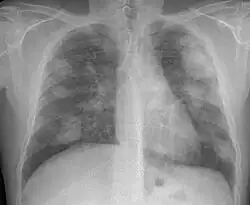

La silicosis complicada se caracteriza por la existencia de masas de Fibrosis Masiva Progresiva, también llamadas masa conglomeradas, con diámetro mayor de 1 cm. Es una enfermedad grave, sobre todo si las masas son de gran tamaño, y disminuye notablemente la esperanza de vida de los pacientes. La evolución de la forma simple a complicada se debe a factores muchas veces desconocidos. Entre los factores conocidos destacan: elevada exposición a sílice, abundante profusión nodular, tuberculosis y enfermedades del colágeno.

La OIT clasifica las masas de FMP) según su diámetro mayor como A (exceden 10 mm), B (aisladamente o sumadas exceden 5 cm) y C (exceden un área equivalente a la de lóbulo superior derecho.

En caso de dudas diagnósticas se puede recurrir a la Tomografía Computada de Alta Resolución (TACAR) que se ha mostrado más sensible y específica para el diagnóstico.[9] Somete al paciente a mucha más radiación que la Rx y no debe usarse como prueba diagnóstica de primer nivel sino para aclarar dudas. La TACAR permite comprobar cómo las masas de FMP se originan frecuentemente en región subpleural de zonas apicales posteriores desplazándose progresivamente de la pleura —signo del desprendimiento—.[3]